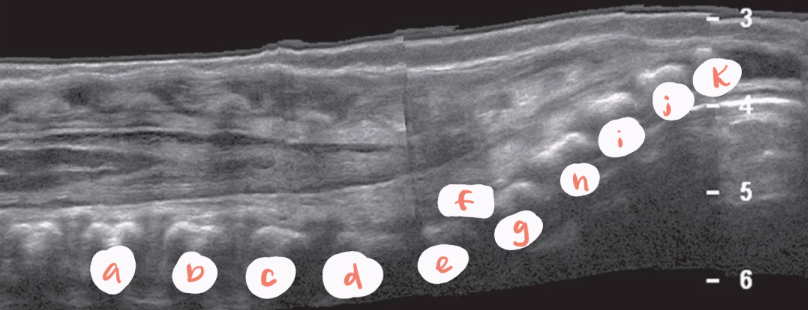

a

L1

b

L2

c

L3

d

L4

e

L5

f

LSJ

g

S1

h

S2

i

S3

J

S4

k

S5

yellow arrow